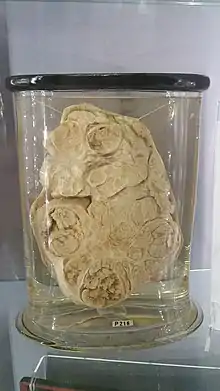

- Pleomorphic adenoma